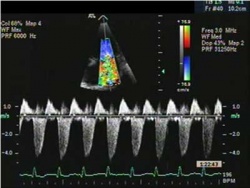

- אקו-לב Echocardiography – אקו לב היא בדיקה פשוטה שאינה פולשנית. בדיקה זו נעזרת בגלי קול כדי לדמות את הלב

היא בודקת את עובי הדופן, גודלו ותפקודו של החדר הימני, ויכולה לבדוק את הלחץ בעורק הריאתי